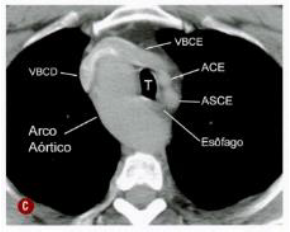

Sobre a anomalia congênita da figura a seguir, assinale a alternativa correta.